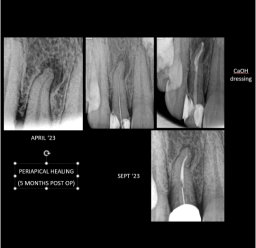

Here is a patient of us who has come with chronic lesion ,with pain due tosevere decay.Eventhough the lesion appeared to be big she was moreconcerned about the aesthetic aspect as it is a front teeth and she doesn’twant to remove the tooth..so her request was to somehow save the toothrather than extraction or any other alternate treatment options .

The prognosis of the tooth was not so good,taken initial diagnostic X ray.Started root canal treatment,opened the access and drainage of the canal

is facilitated.The access is kept open for 2 weeks with antibioticprophylaxis.

After 2 weeks, working length is taken and proper biomechanicalpreparation is done with lots of irrigation.Intracanal medicament such as

calcium hydroxide is placed till the apex to control the infection.Sinus tract

is traced with Gutta percha point .

Repeated the new calcium hydroxide dressing in every 2 weeks .Anoticable change in the regression of periapical lesion is noted along with the healing of sinus tract

Completion of obturation done with rotary endodontic files and post and core isplaced to reinforce the tooth crown structure. This series of xrays shows ,the progression of this case that how can a hugeabscess can be managed with proper treatment and follow ups without doingapicoectomy procedure.